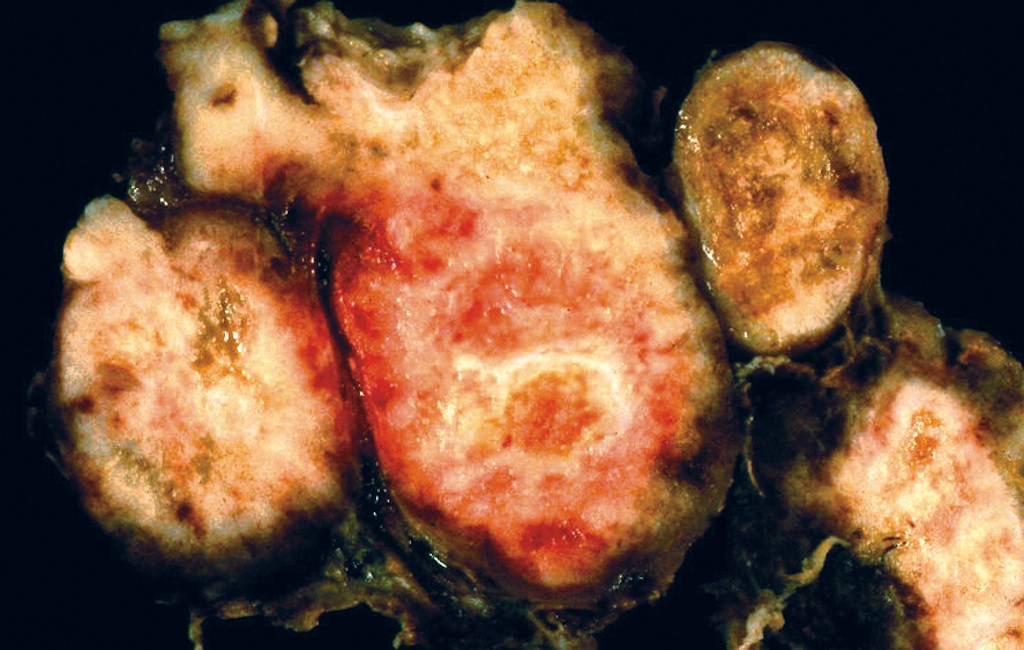

Gross description

- Sporadic: typically presents as a single circumscribed but nonencapsulated, gray-tan mass

- Familial: generally bilateral / multiple foci

- Solid, gray-tan-yellow, firm, may be infiltrative

- Larger lesions have hemorrhage and necrosis, tumor usually in mid or upper portion of gland (with higher density of C cells)

- < 1 cm in size is called microcarcinoma; if < 0.5 cm, associated with a complete absence of clinically detectable metastatic disease (Ann Surg Oncol 2009;16:2875)

Gross images

Contributed by Mark R. Wick, M.D.

AFIP images